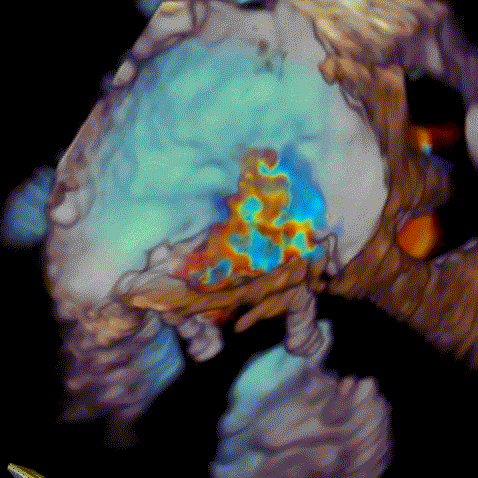

瓣中瓣植入前

二尖瓣重度反流

术后左室造影无反流